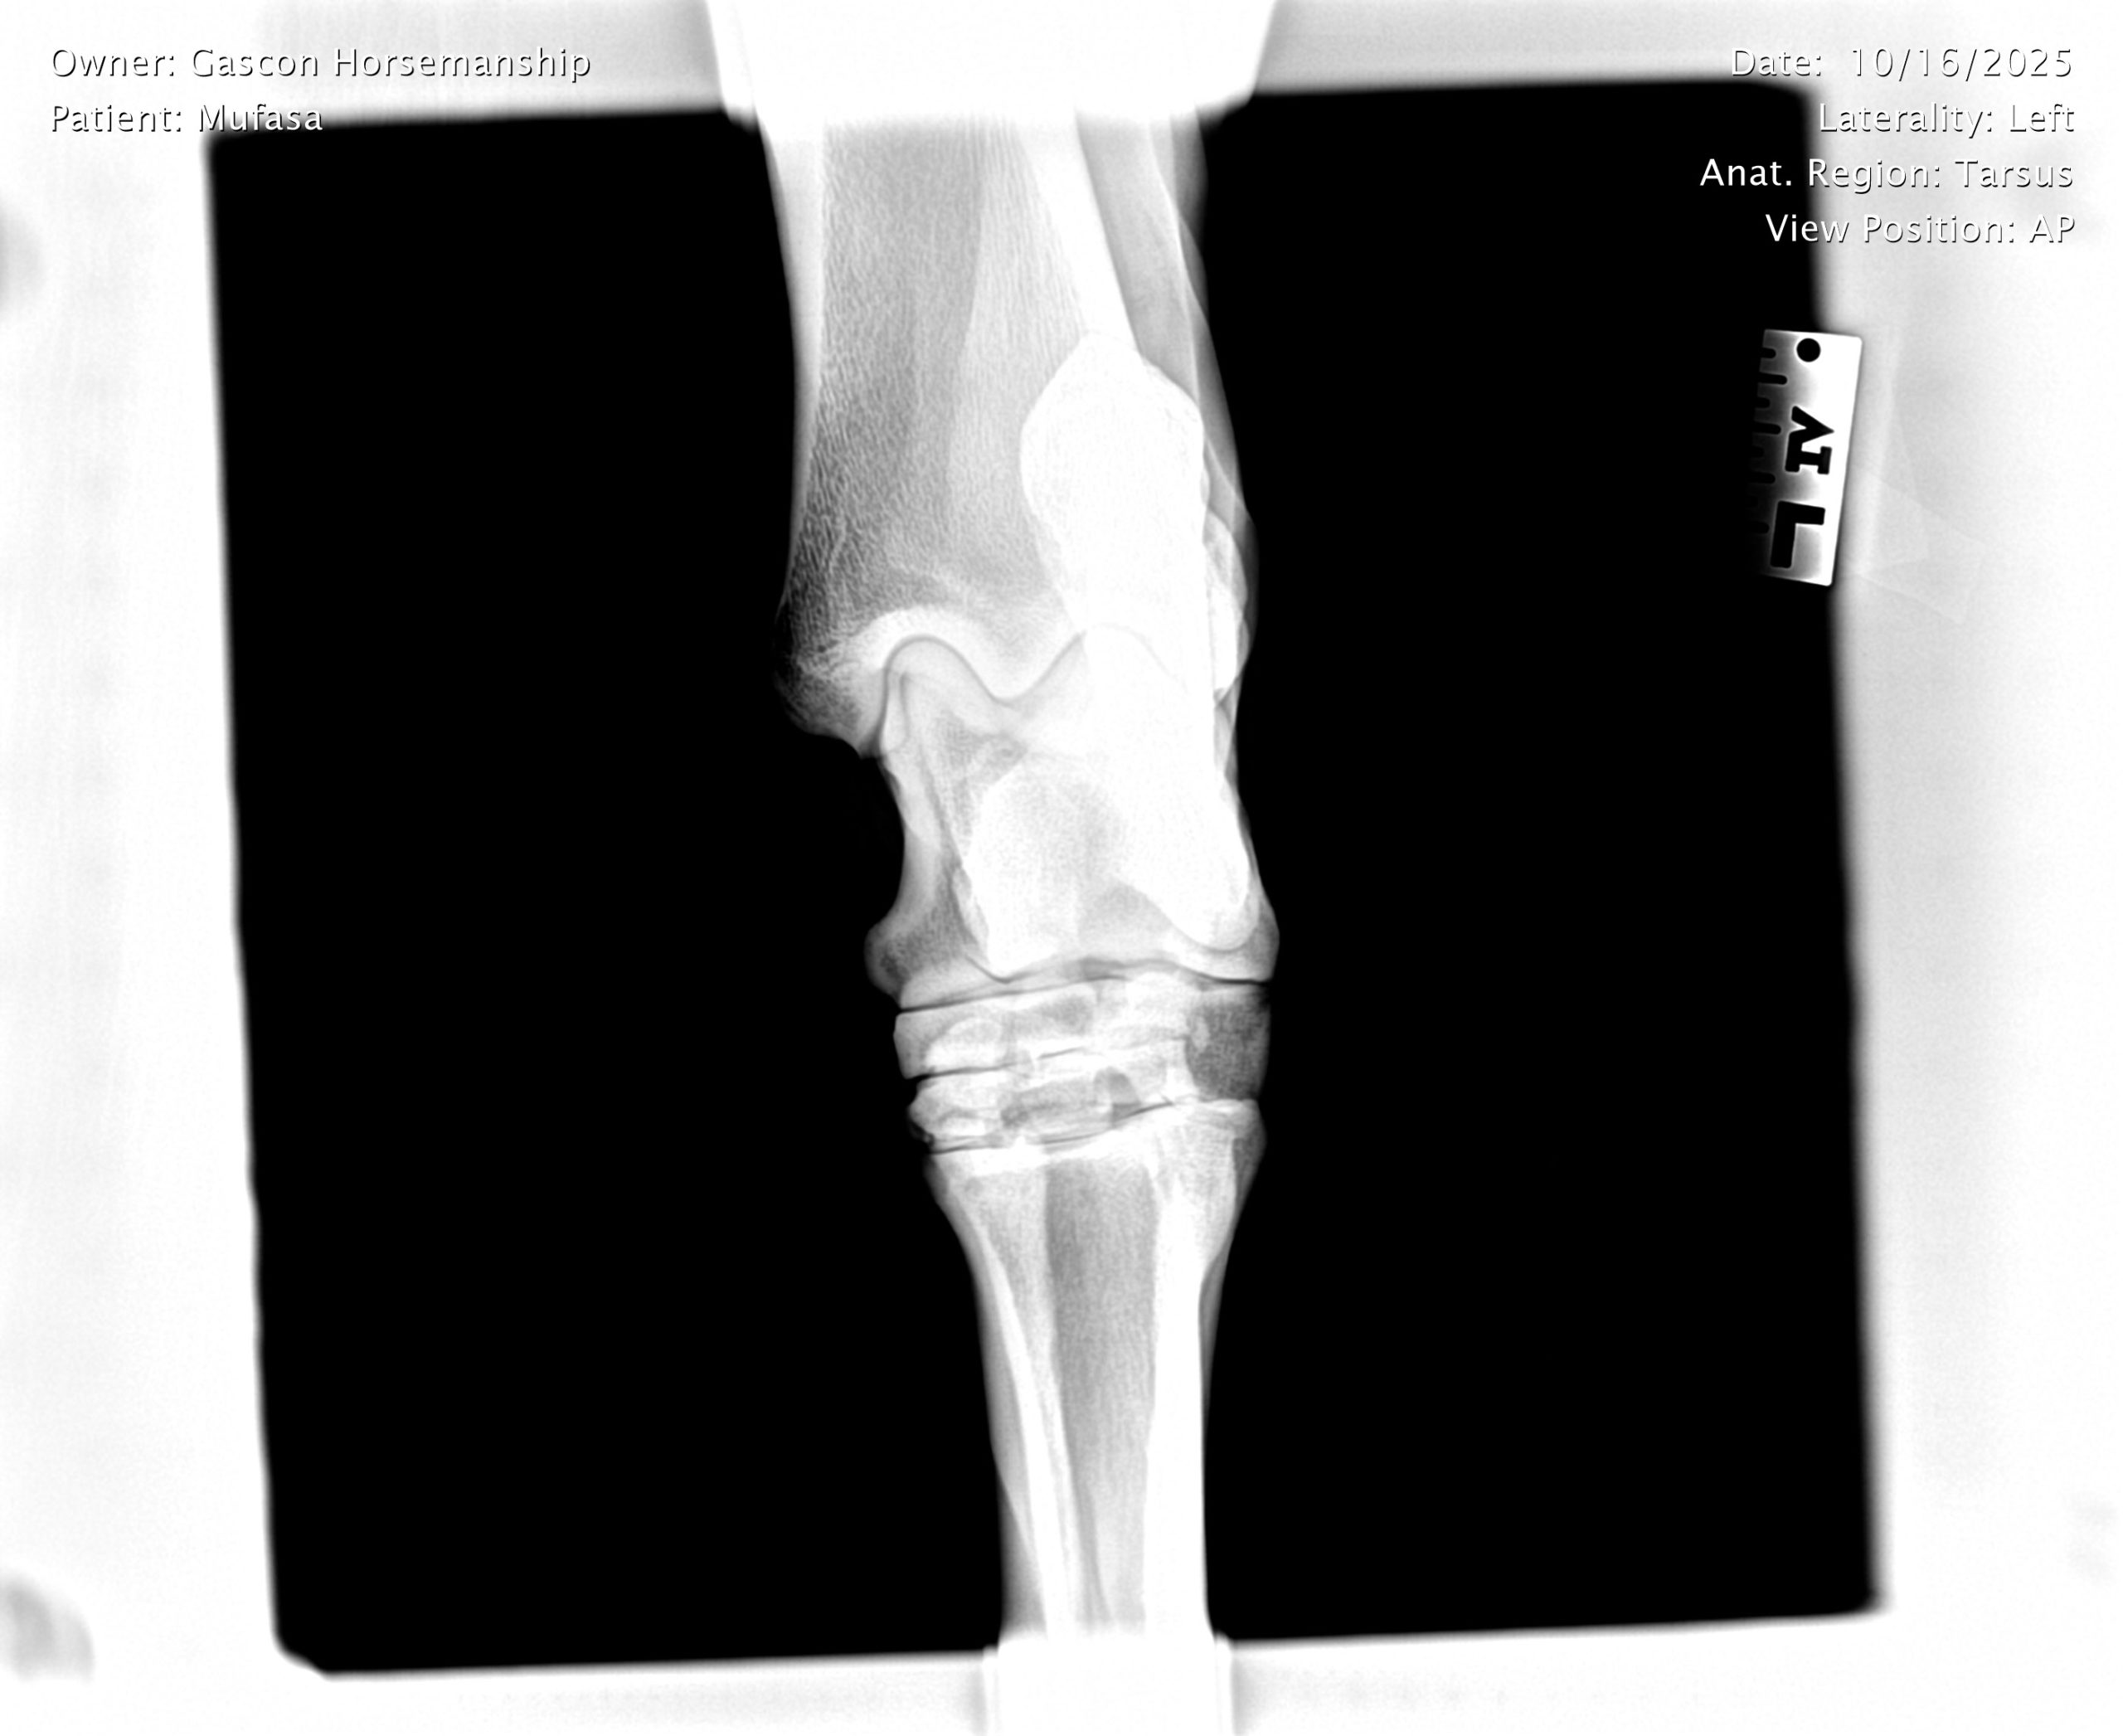

He already has a full pre-purchase exam on file, complete with 25 X-rays included in his album.